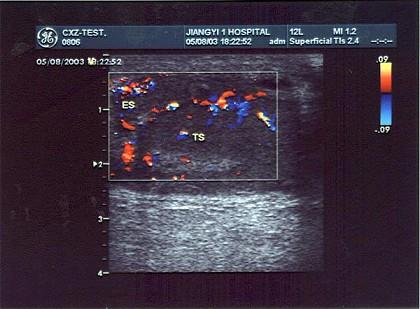

某患者阴囊部疼痛不适,超声声像图如下,最可能的诊断为?(?)A.附睾炎B.睾丸炎C.睾丸肿瘤D.附睾结核E.附睾肿瘤

问题 某患者阴囊部疼痛不适,超声声像图如下,最可能的诊断为?(?)

选项 A.附睾炎 B.睾丸炎 C.睾丸肿瘤 D.附睾结核 E.附睾肿瘤

答案 A